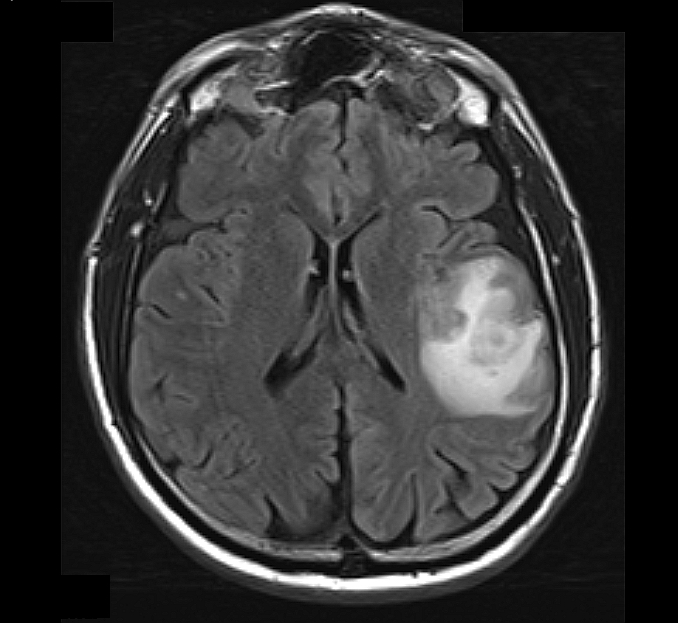

Radiology description

- MRI: T2 / fluid attenuated inversion recovery (FLAIR) bright infiltrative lesion(s) with postcontrast T1 showing irregular peripheral rim enhancement with central necrosis

- May cross the corpus callosum

- May be multifocal

- Lack of contrast enhancement may be observed in molecularly defined glioblastoma

- Certain subtypes (i.e., gliosarcoma, epithelioid, giant cell) may appear well circumscribed (Neurosurg Rev 2021;44:3335, Eur Radiol 2019;29:429, Surg Pathol Clin 2020;13:249)